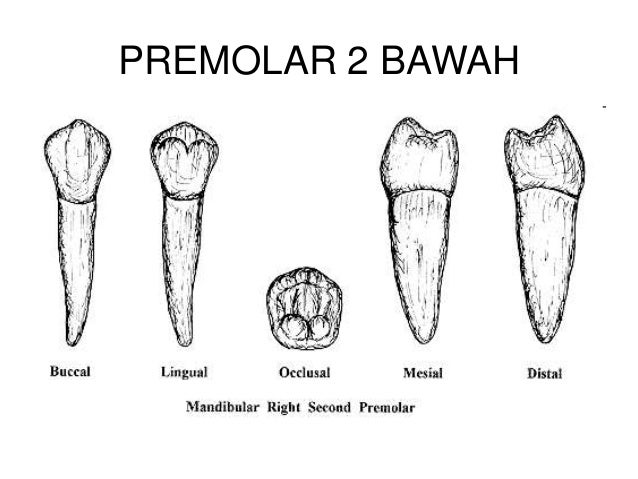

2. dental anatomi gigi permanen ..

2. dental anatomi gigi permanen ..

2. dental anatomi gigi permanen ..

2. dental anatomi gigi permanen ..

10. morfologi gigi permanent rahang bawah

10. morfologi gigi permanent rahang bawah

Anatomi Gigi Premolar

Anatomi Gigi Premolar

klasifikasi gigi molar dan premolar pada dental